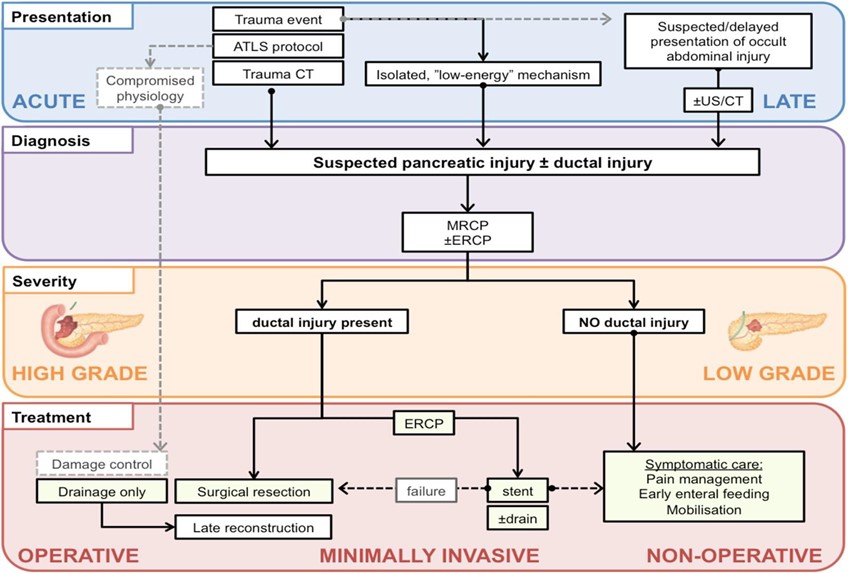

Blunt abdominal trauma is more challenging than penetrating trauma, where the decision to operate is usually straightforward. All abdominal trauma is managed one of three ways:

- Operative

- Non-operative management (NOM) with IR

- NOM without IR.